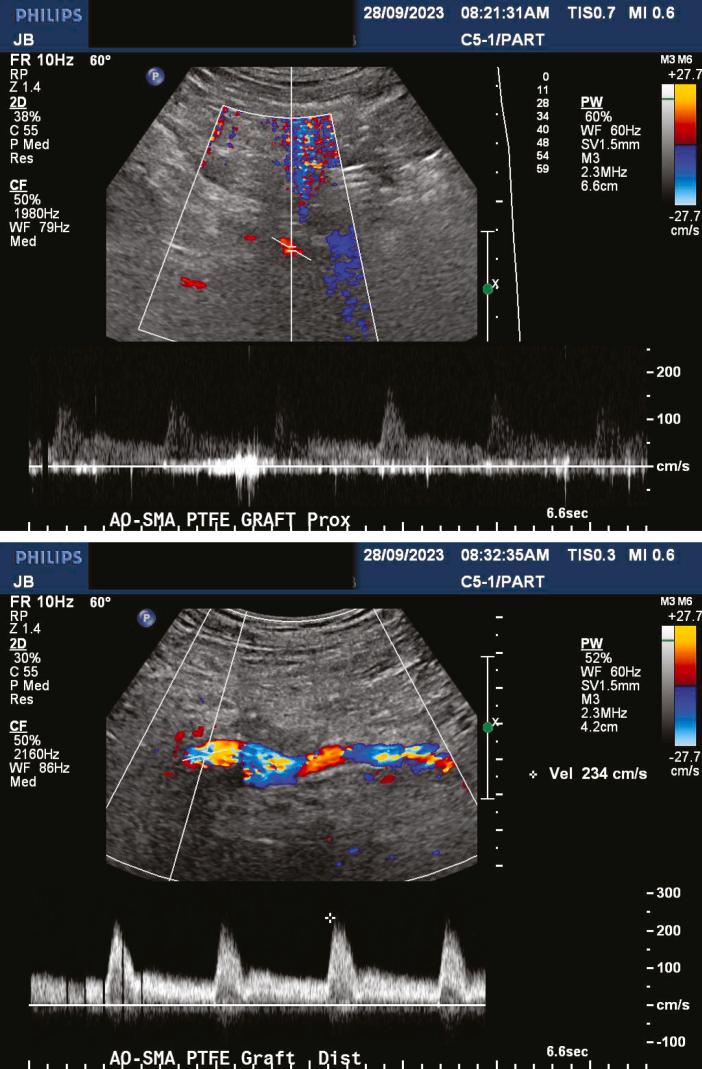

Inferior mesenteric artery (IMA) aneurysms account for approximately 1% of visceral artery aneurysms and can occur secondary to high flow because of occlusive disease in other mesenteric arteries. We describe the case of a 79-year-old man who presented with a 3.3-cm IMA aneurysm and chronic total occlusions of the celiac artery and superior mesenteric artery (SMA). After an unsuccessful attempt at endovascular SMA recanalization, he underwent an uncomplicated retrograde aorta to SMA bypass and antegrade aorta to IMA bypass. We propose that an aorta to IMA bypass after SMA revascularization is safe and effective to treat suspected high-flow IMA aneurysms.